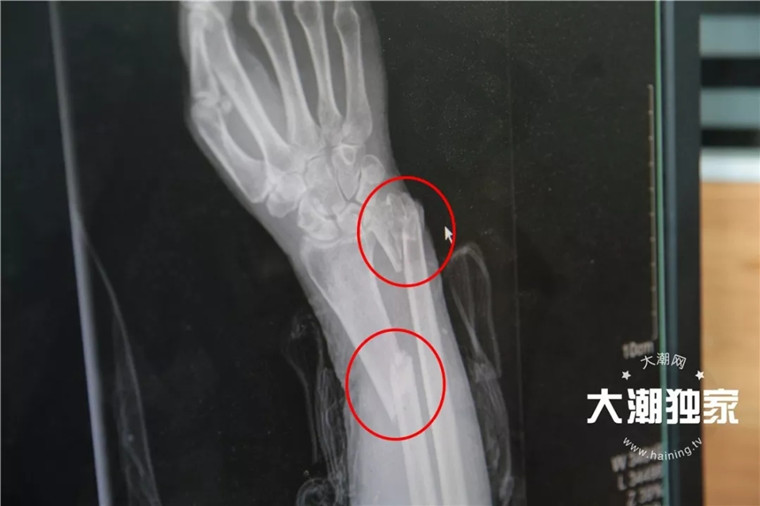

交警说

老太当时右手腕有点骨折

额头磕在台阶上,流着血

意识还是蛮清醒的